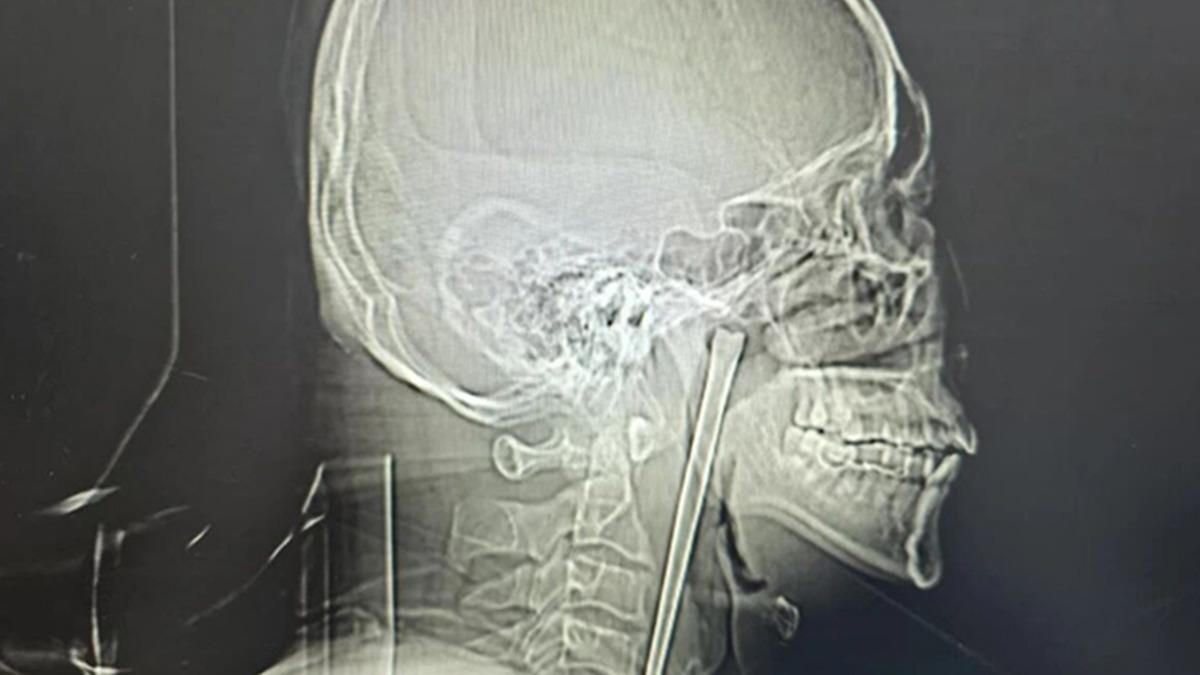

Doktorlar, Wang'ın boğazını incelediklerinde dokularda herhangi bir kanama veya iltihaplanma görmediler. Ancak çekilen röntgen filmi gerçeği tüm çıplaklığıyla ortaya koydu: Boğazın iç kısımlarına yerleşmiş, 12 santimetre uzunluğunda, metal bir şaft duruyordu. Çubuk, her an hayati damarlara zarar verebilecek veya doku hasarına yol açabilecek bir saatli bomba gibiydi.

Dr. Huang Weipeng liderliğindeki sağlık ekibi, hastanın ameliyat korkusunu yenmek için titiz bir plan hazırladı. Boyun bölgesinde kalıcı bir hasar bırakmamak adına minimal invaziv (kapalı cerrahi) yöntem tercih edildi. Ağız içinden yapılan hassas bir müdahaleyle, 12 santimetrelik paslanmaz çelik çubuk, çevre dokulara zarar verilmeden tek parça halinde çıkarıldı.